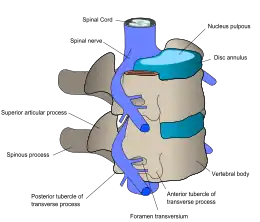

The lumbar (or lower back) region is the area between the lower ribs and gluteal fold which includes five lumbar vertebrae (L1–L5) and the sacrum. In between these vertebrae are fibrocartilaginous discs, which act as cushions, preventing the vertebrae from rubbing together while at the same time protecting the spinal cord. Nerves come from and go to the spinal cord through specific openings between the vertebrae, receiving sensory input and sending messages to muscles. Stability of the spine is provided by the ligaments and muscles of the back and abdomen. Small joints called facet joints limit and direct the motion of the spine.[35]

An intervertebral disc has a gelatinous core surrounded by a fibrous ring.[37] When in its normal, uninjured state, most of the disc is not served by either the circulatory or nervous systems – blood and nerves only run to the outside of the disc.[37] Specialized cells that can survive without direct blood supply are in the inside of the disc.[37] Over time, the discs lose flexibility and the ability to absorb physical forces.[28] This decreased ability to handle physical forces increases stresses on other parts of the spine, causing the ligaments of the spine to thicken and bony growths to develop on the vertebrae.[28] As a result, there is less space through which the spinal cord and nerve roots may pass.[28] When a disc degenerates as a result of injury or disease, the makeup of a disc changes: blood vessels and nerves may grow into its interior and/or herniated disc material can push directly on a nerve root.[37] Any of these changes may result in back pain.[37]